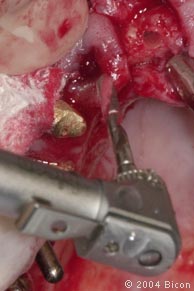

17. |

预备牙槽骨的过程中,医生用手指鉴测颊侧骨组织,可见4.5mm的银色手动扩孔钻收集到的骨组织。 |